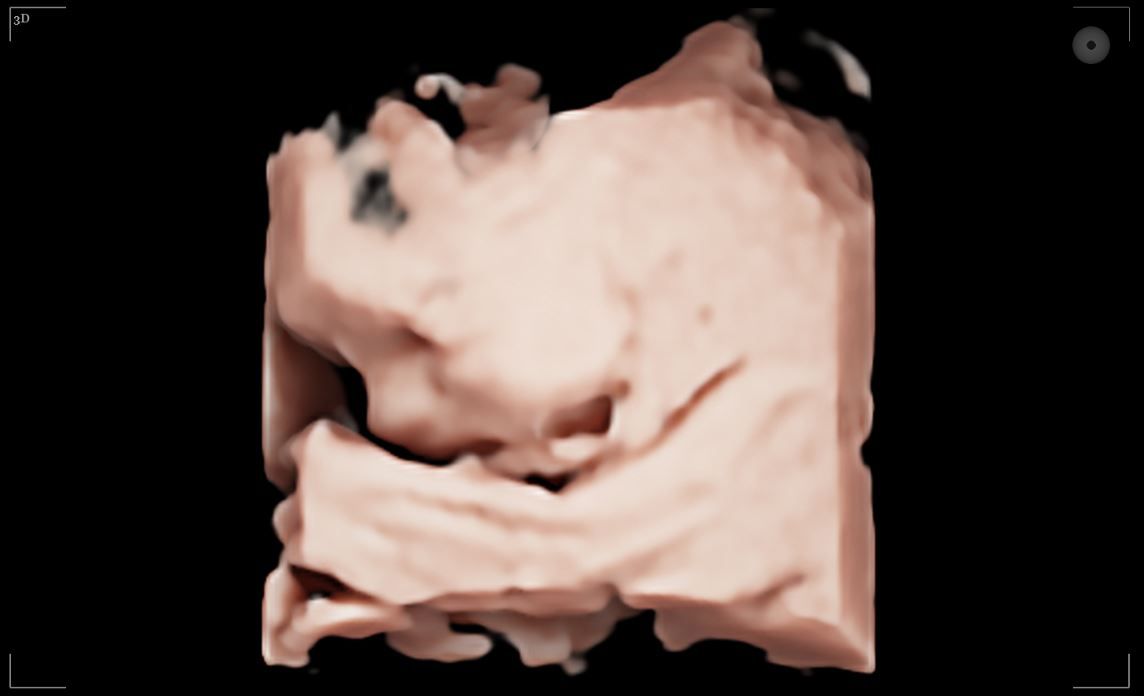

3D Echo

Een stilstaand beeld van een levensechte weergave van jouw kindje. Hierbij zijn duidelijke contouren zichtbaar van bijvoorbeeld de vingertjes, het neusje en de lipjes.

4D Echo

Je ziet 'live' wat je baby doet: gapen, schoppen, draaien, duimzuigen... Met een 4D echo zie je beweging én kleur. De meest realistische weergave!